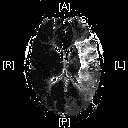

fig. 2: BEFORE the procedure: a perfusion MRI showing the left middle cerebral artery territory, the white area is where the blockage occur.

A perfusion MRI study was conducted and determined the area of the impaired blood flow, figure 2 shows the left middle cerebral artery territory, the white area is where the blockage occur; here, the connecting vessels of the right to the left side at the base of the brain only allowed some flow into the first portion of the left middle cerebral artery (fig. 1).